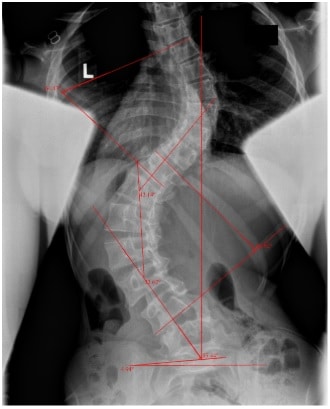

الأشعة السينية (X-Ray): لقياس زاوية انحناء العمود الفقري (زاوية كوب – Cobb Angle).

الأشعة ثلاثية الأبعاد أو التصوير EOS في الحالات المعقدة.